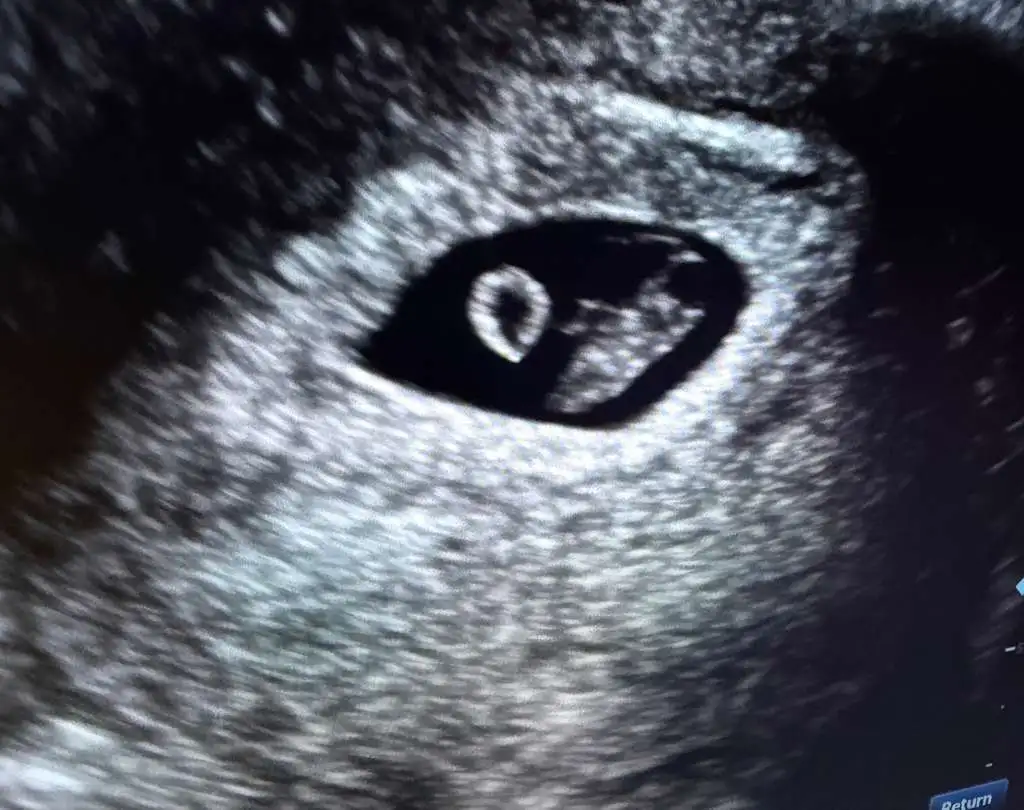

Pregnancy Confirmation

5-12 week

This early ultrasound is performed to confirm pregnancy, visualize the gestational sac, yolk, and fetal pole.